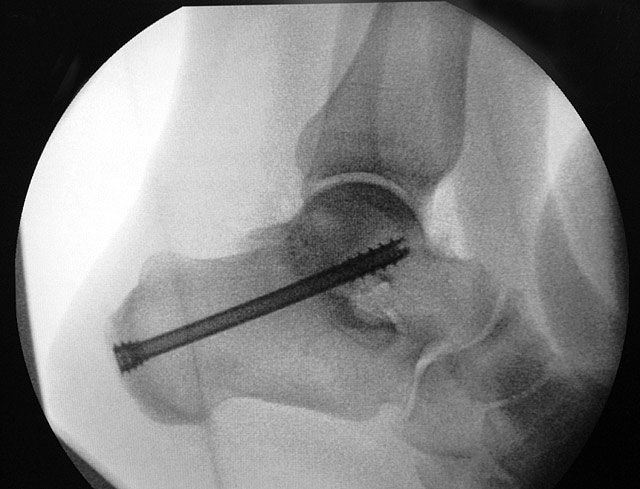

Je nach Operationsziel wird die Arthrodese des Subtalargelenks in verschiedenen Modifikationen durchgeführt. Ist der Rückfuß orthograd ausgerichtet, so erfolgt sie als in situ Fusion, d.h. ohne Korrektur Änderung der Rückfussachse. Liegt eine Rückfuß-Fehlstellung vor, kann diese durch ein additives oder substraktives knöcherndes Vorgehen korrigiert werden 12. Die Fixation der Arthrodese erfolgt üblicherweise mit (kanülierten) Schrauben die über den Tuber calcanei eingebracht werden 3. Eine zweite Schraube zur Sicherung der Rotationsstabilität wird optional über den Processus anterior calcanei im Talushals verankert 4. Der am häufigste verwendete Zugang zum unteren Sprunggelenk verläuft lateral subfibular, alternative Zugänge sind medial oder posterior möglich 56. Ist keine relevante Korrektur notwendig kann der Eingriff auch arthroskopisch durchgeführt werden 78.

Ziel der Korrektur ist eine Reposition des Kalkaneus in eine physiologische 5° valgus Stellung. Eine Überkorrektur in Varus ist in jedem Fall zu vermeiden. Die Stellung wird anschließend mit K-Drähten fixiert, über die kanülierte Schrauben eingebracht werden können."> 155.</li>

Ziel der Korrektur ist eine Reposition des Kalkaneus in eine physiologische 5° valgus Stellung. Eine Überkorrektur in Varus ist in jedem Fall zu vermeiden. Die Stellung wird anschließend mit K-Drähten fixiert, über die kanülierte Schrauben eingebracht werden können." srcset="/assets/images/1/3-9tsh2b2m85xxjf3.jpg 1x, /assets/images/q/3-q5j2bj6y0h8725z.jpg 1.5x, /assets/images/k/3-h9kd23kj30b48p9.jpg 2x" width="270" height="240" loading="lazy">

Abbildung 3

Schraubenfehllage: Bei der intra-operative Röntgen-Kontrolle muss der Fuß exakt seitlich und das obere Sprunggelenk ap eingestellt werden, um die korrekte Lage der Schrauben beurteilen zu können.